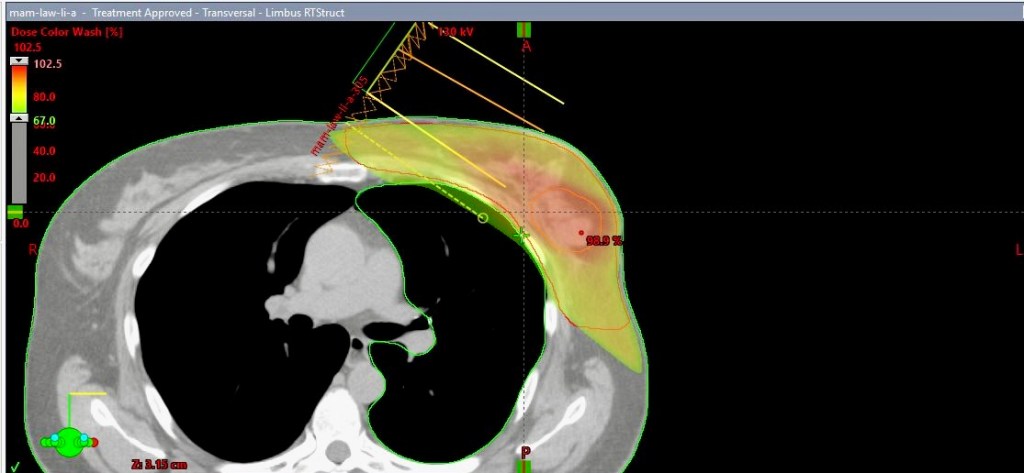

Passgenau im allerengsten Sinne

Für die spätere Strahlenbehandlung werden im Vorfeld Bereiche und Winkel festgelegt und so passgenau berechnet, wie man es sich kaum vorstellen kann. Er zeigt mir das anhand meiner eigenen Bilder und als wir nach einer ganzen Weile unterbrochen werden, sagt er: „An dieser Stelle wurden erst zwei Tage lang Berechnungen für dich gemacht. Da kommt noch mehr als die doppelte Zeit dazu.“, meint Dr. Koppe und fügt hinzu: „Ein weiterer sehr wichtiger Vorgang ist, nach all der Rechnerei und noch lange bevor wir unsere Patientinnen und Patienten mit den Strahlen behandeln, dass wir zum Einen, so wie es auch bei den Tumorkonferenzen ist, zusammensitzen und nach dem Vier-Augen-Prinzip gemeinsam mit Technikern und Kollegen beraten, ob der Behandlungsplan zu 100 % stimmig ist. Zum Anderen erstellen wir, bevor wir die Leute bestrahlen, auf dem Bestrahlungsuntergrund in einem Probedurchlauf mit dem Gerät eine Art Blaupause. Dabei entsteht beispielsweise dein ganz individuelles Behandlungsmuster. Dieses Vorgehen sichert noch ein weiteres Mal ab, dass du genau die Behandlung bekommst, die du benötigst. Nicht mehr und nicht weniger.“